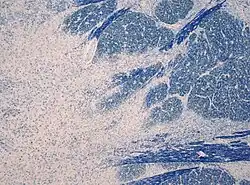

Die Zentrale pontine Myelinolyse (ZPM) (lat. pons, Brücke, pontine die Brücke betreffend; griech. μῦελόν, myelon, Mark, λύσις, lýsis, Auflösung) ist eine neurologische Erkrankung, bei der es zu einer Schädigung der Umhüllung von Nervenfasern besonders im Pons (Hirnstamm) kommt. Sie wird durch zu schnelle Korrektur eines krankhaft verminderten Natriumspiegels (Hyponatriämie) im Organismus hervorgerufen.

Als Variante der ZPM gilt die extrapontine Myelinolyse. Dabei kommt es zu Demyelinisierungen in Kleinhirn, Basalganglien, Capsula interna, Balken und in der Nähe der Ventrikel. Beide Formen werden als osmotisch demyelinisierende Erkrankung bzw. osmotisches Demyelinisierungssyndrom zusammengefasst, sie können auch gleichzeitig auftreten.

Bei einem Verlust von Natrium aus dem Blut sinkt der Natriumspiegel langsam auch in allen anderen Kompartimenten des Körpers. Dies wird bei langsamem Absinken meist gut vertragen. Wird die Hyponatriämie festgestellt und parenteral durch Infusion ausgeglichen, kommt es je nach Geschwindigkeit des Anstiegs des Natriumspiegels zu einer Verschiebung von Wasser aus dem Gewebe ins Blut, da Natrium nicht so rasch in die anderen Kompartimente (besonders in die Zellen) diffundieren kann. Die Dehydratisierung (Entwässerung) des Gehirns führt über einen unbekannten Mechanismus zu einer Zerstörung der Myelinscheiden. Der Vorgang wird als osmotische Demyelinisierung bezeichnet.